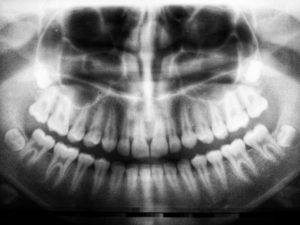

tandproteser stockholm